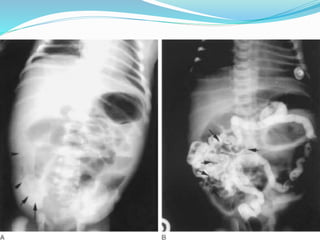

 Abdominal X-Ray…

 Barium Enema…

Day 1 6th Week Showing Transition Zone

 The Presence Of Barium In The 24-hour Delayed Film

Also Suggests Hirschsprung's Disease.

Day 1 6thWeek Showing Transition Zone

 The PresenceOf Barium In The 24-hour Delayed Film Also Suggests Hirschsprung's Disease.